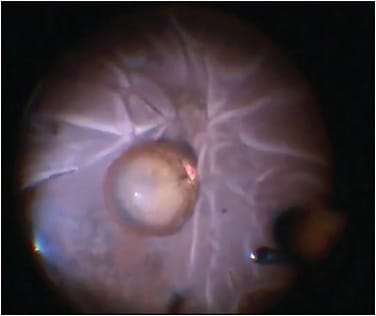

Once the anterior chamber is free of prolapsed vitreous, any smaller nuclear or epinuclear fragments still available anterior to the posterior lens capsule may be carefully removed (Figure 1). Dispersive viscoelastic can be used to bring fragments into the iris plane. This viscoelastic can be injected through a limbal incision or through the pars plana (posterior assisted levitation [PAL]).7 In general, the cataract surgeon may wish to avoid mechanical PAL with a spatula or other device, as such maneuvers may inadvertently cause further retinal traction.